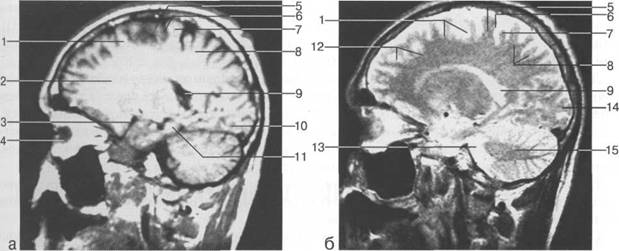

Задняя череп 13513u2010n 85;ая ямка представляет собой часть основания череп 13513u2010n 72;, ограниченную централь

Следует отметить, что в настоящее время оптимальным методом исследования структур задней череп 13513u2010n 85;ой ямки является МРТ, которая, в отличие от КТ, лишена артефактов от кост

Мозжечок заполняет практически весь объем задней череп 13513u2010n 85;ой ямки. Его поперечный раз

височная доля; 17 - полушарие мозжечка; 18 - |

Следует остановиться на анатомии подпаутинных пространств задней череп 13513u2010n 85;ой ямки IV 20 мм. Между основанием череп 13513u2010n 72; и нижней поверхностью мозга от большого затылочного отверстия вдоль ската и спинки турецкого седла простирается задняя базальная цистерна. В зави IV

ные извилины (рис. 1.10). Структуры средней череп 13513u2010n 85;ой ямки ограничены спереди малым крылом основной кости, снизу - большим крылом, сзади - передней поверхностью пирами «edge» «bone»

Содержимое средней череп 13513u2010n 85;ой ямки представлено базальными отделами височной доли.